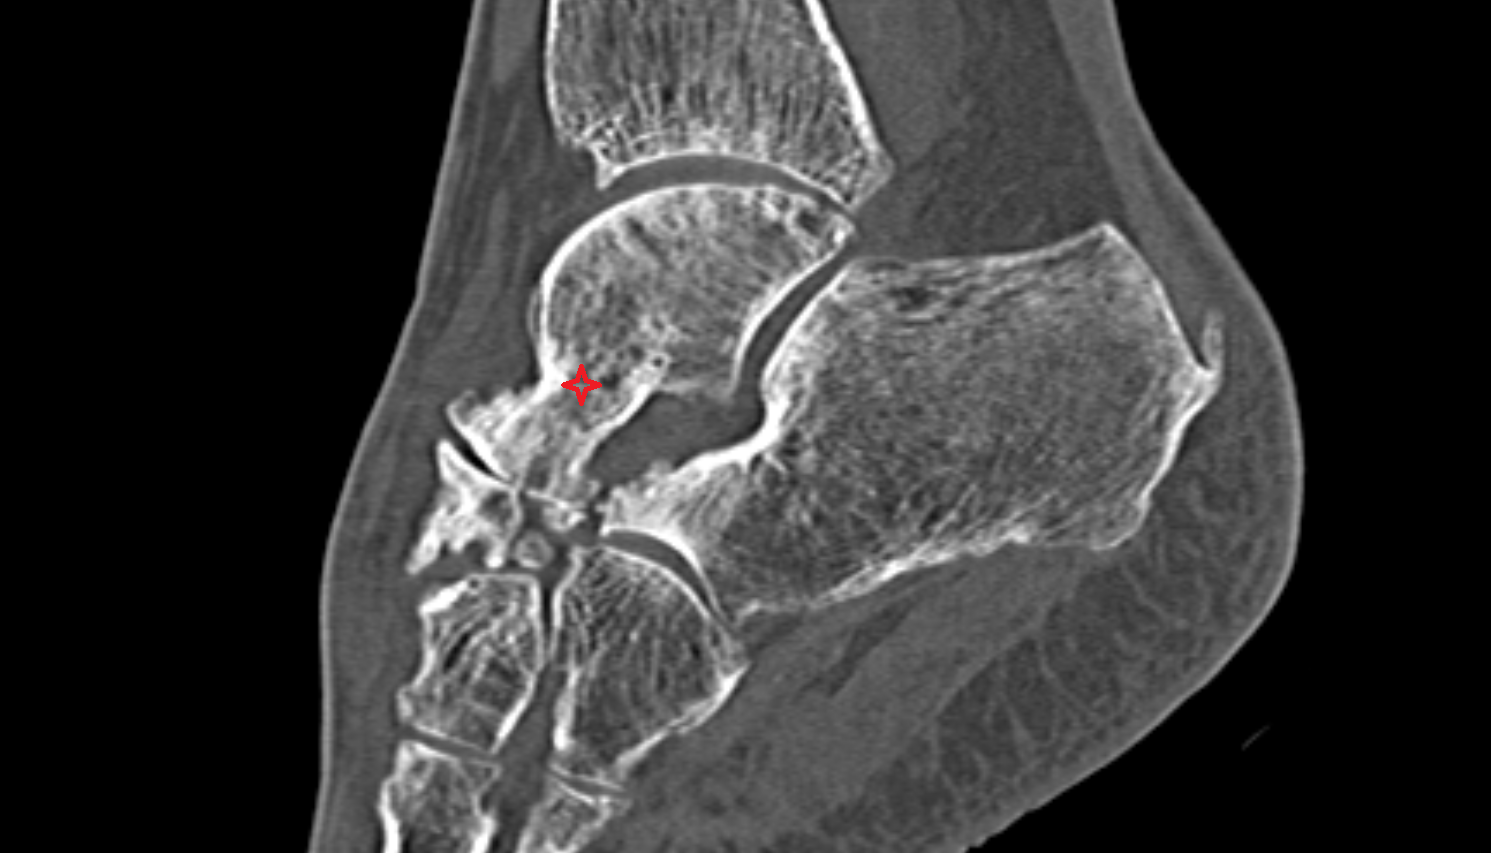

- Talus

- Head of talus

- Body of talus

- Neck of talus

- Calcaneus

- Ankle joint

- Talocalcaneal joint

- Talocalcaneonavicular joint